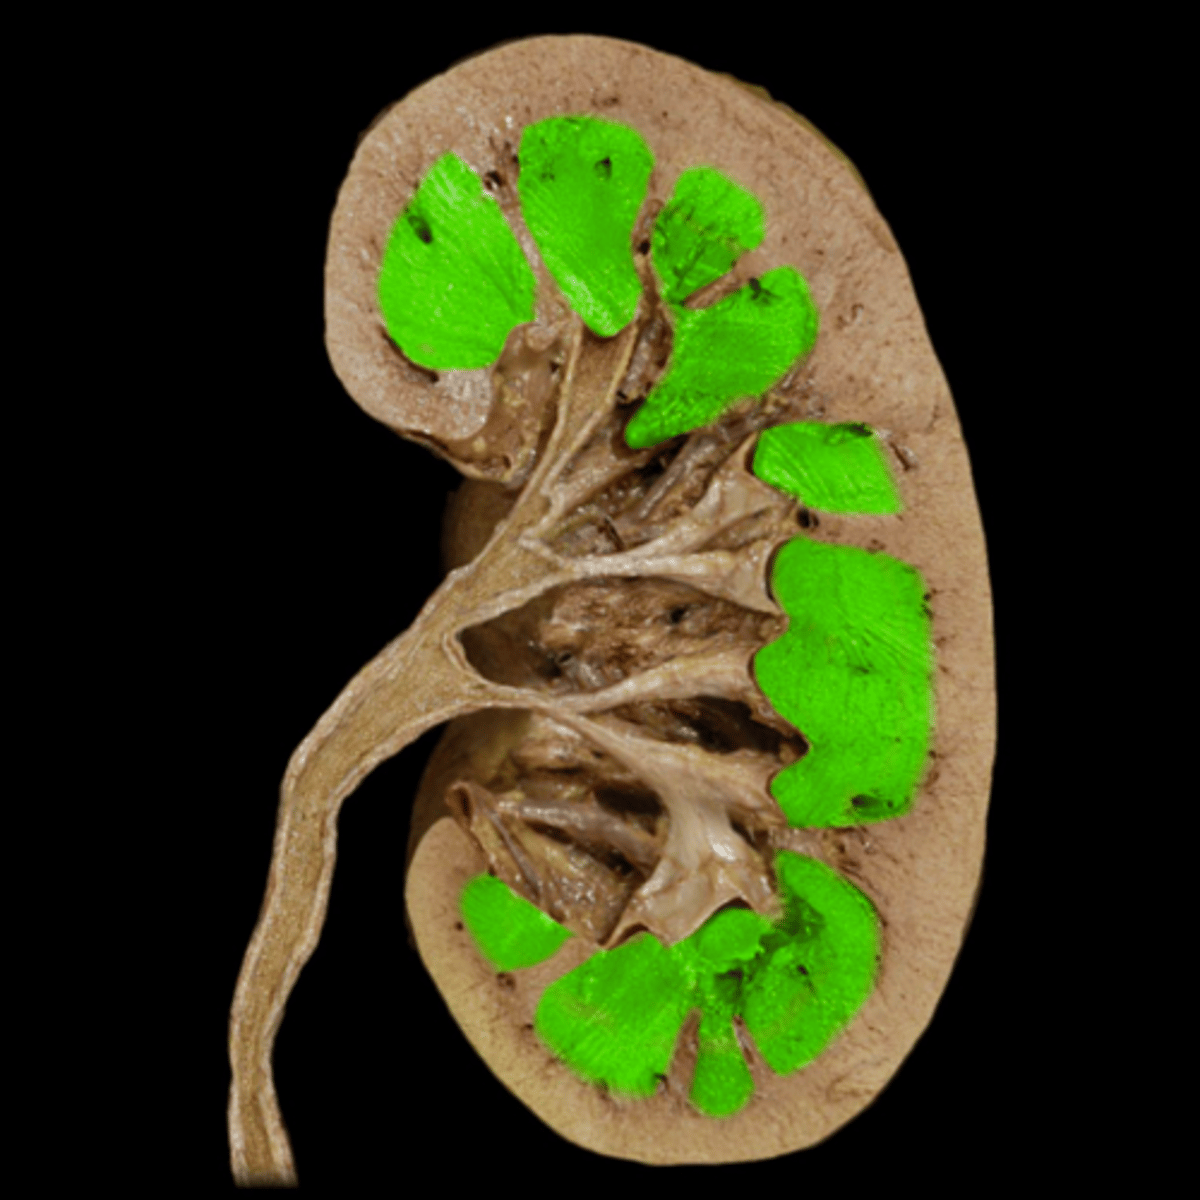

Renal Medulla

Papilla

Renal Column

Minor Calyx

Major Calyx

Renal Pelvis

Renal Hilum